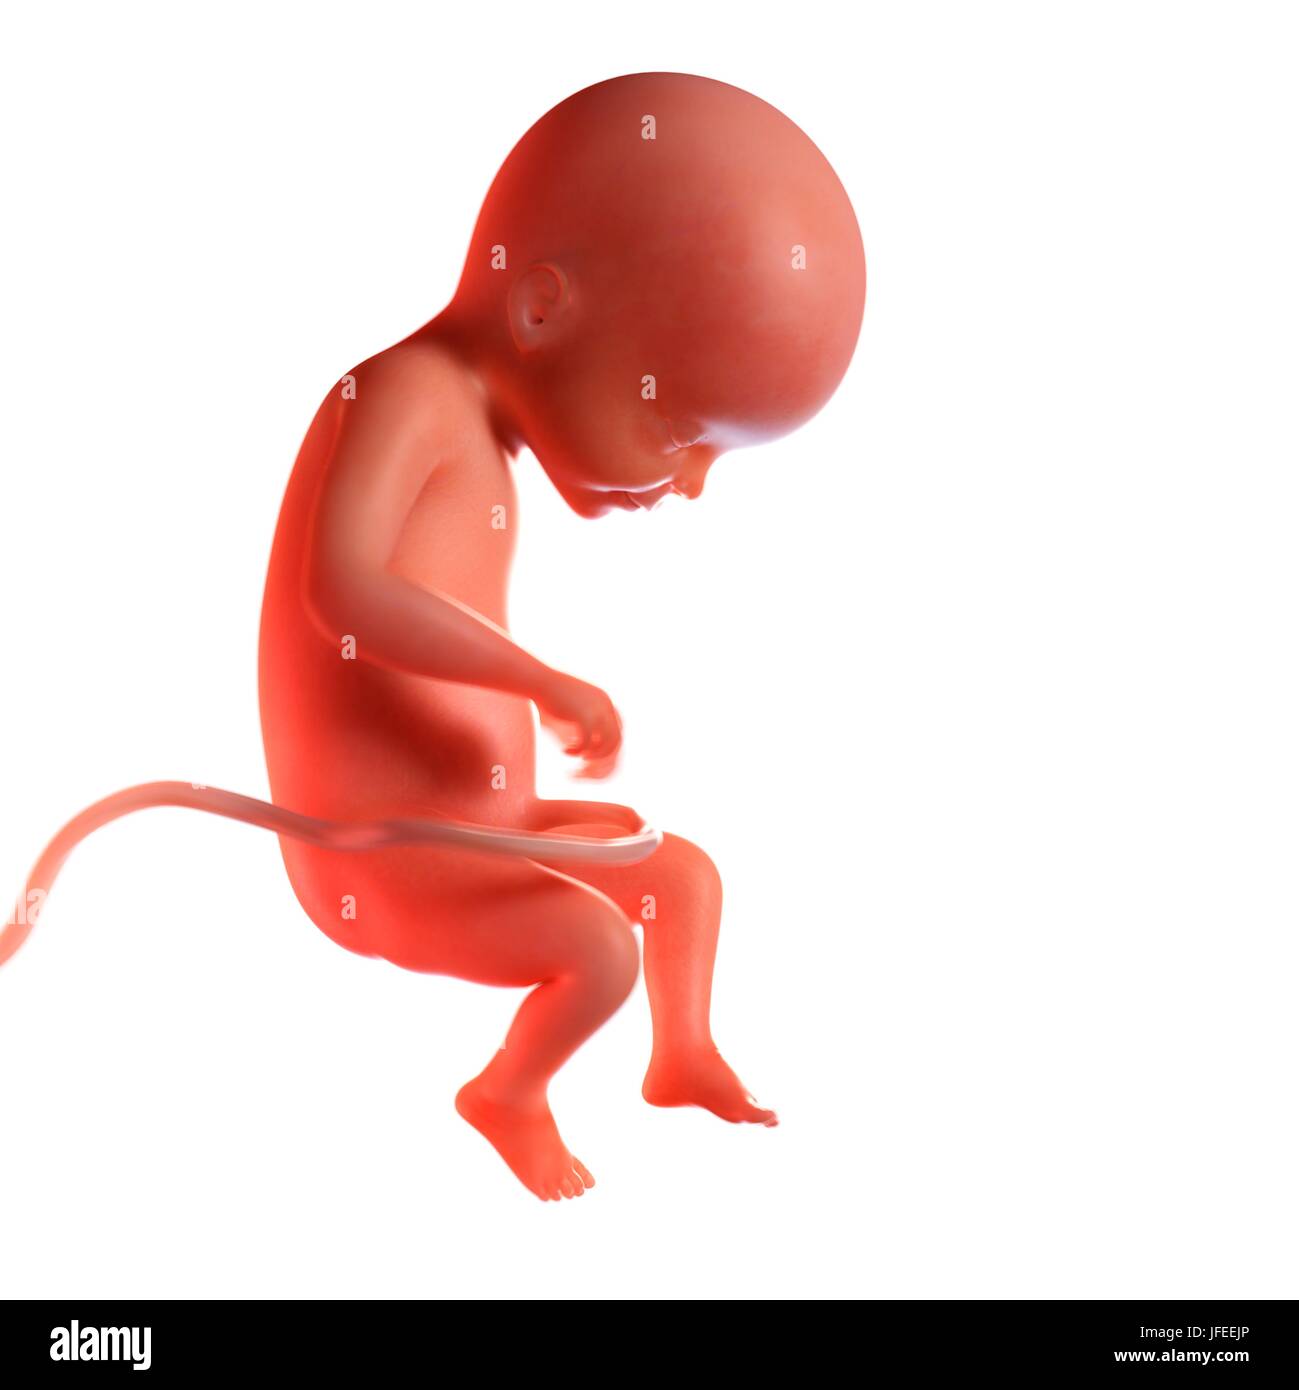

Feto A 22 Settimane Artwork Foto Stock Alamy

Feto Umano Eta 22 Settimane Illustrazione Foto Stock Alamy